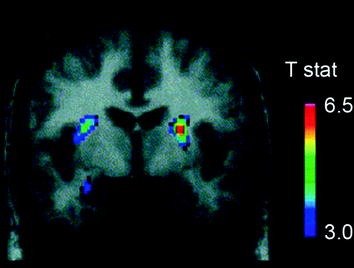

Several neurotransmitters, including DA, cannabinoids, opioids, and serotonin, as well as hormones and neuropeptides involved in homeostatic regulation of food intake, such as insulin, orexin, leptin, and ghrelin, have been implicated in the rewarding effects of food (Atkinson 2008; Cason et al. 2010; Cota et al. 2006). Of these, DA has been the most thoroughly investigated and is the best characterized. Experiments in rodents have shown that, upon first exposure to a food reward, the firing of DA neurons in the VTA increases with a resulting increase in DA release in NAc (Norgren et al. 2006). Similarly, in healthy, normal-weight human subjects, the ingestion of palatable food has been shown to release DA in the dorsal striatum in proportion to the ratings of meal pleasantness (Small et al. 2003) (Fig. 3). However, and as seen in studies with drug abusers, food-induced increases in striatal DA alone cannot explain the difference between normal food intake and excessive compulsive food consumption since these also occur in healthy individuals who do not eat excessively. Thus, as is the case for addiction, downstream adaptations are likely to be involved in the loss of control over food intake.

Fig. 3 Dopamine release induced by feeding. Coronal section from the T-map of statistically significant reductions in [11C]raclopride’s binding potential (BP) following feeding. The colour bar represents the t statistic values. (Reprinted with permission Small et al. 2003)